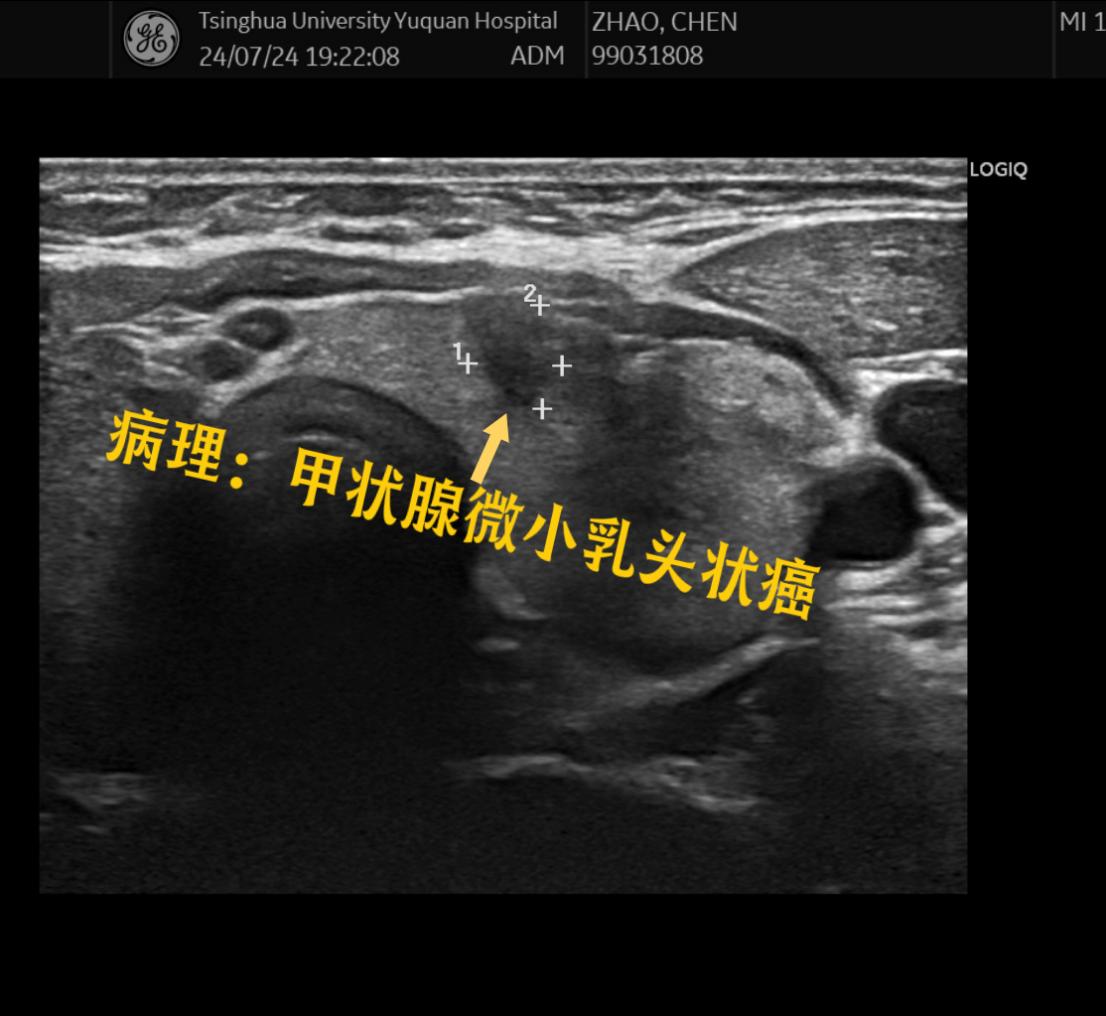

(5)未侵犯甲状腺被膜,无淋巴结转移的微小乳头状癌。